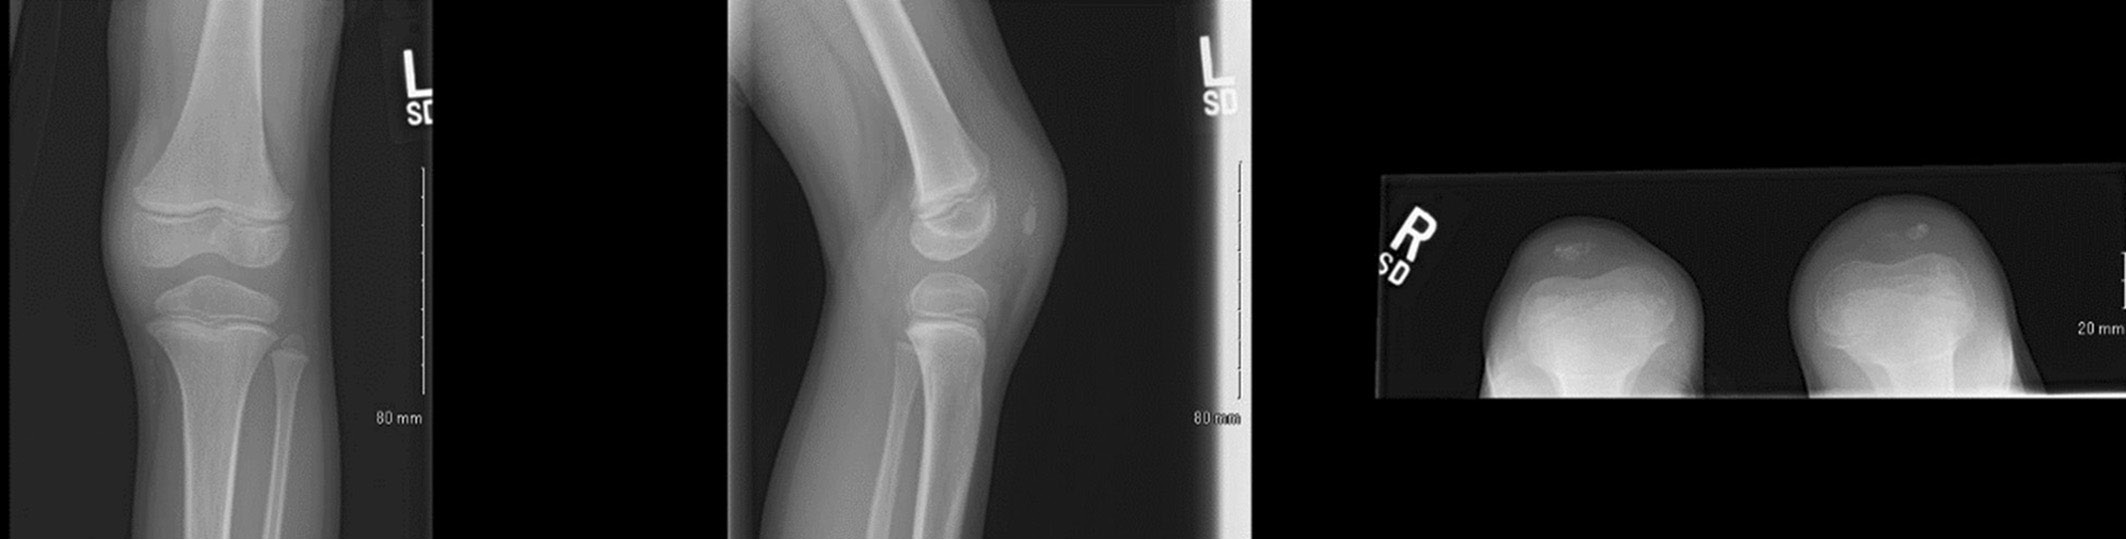

Three days following completion of antibiotics, the patient formally presented to the healthcare system at the ED with his family. He had worsening knee swelling and pain without constitutional signs or symptoms. He localized his pain to his anterior knee just distal to his patella; he could bear weight through the limb but ambulated with a limp. Evaluation of the left knee showed the skin to be without wounds or erythema but with slight warmth compared to the contralateral knee. There was significant prepatellar swelling compared to the contralateral side. There was tenderness to palpation of the prepatellar region but no medial or lateral joint line tenderness. He had pain with terminal flexion but denied pain with axial loading or hip range of motion. He was able to actively extend the knee to 0 degrees and actively flex to approximately 130 degrees. Laboratory evaluation revealed a white blood cell (WBC) count of 10.7, erythrocyte sedimentation rate (ESR) of 36, C-reactive protein (CRP) of 2.6, and negative Lyme test. His left knee radiographs were significant for prepatellar effusion without evidence of a knee effusion (Figure 1). A left knee ultrasound was obtained which showed a 4.2 × 1.3 cm hypoechoic collection suggesting prepatellar bursitis (Figure 2).

Figure 1. Left knee anterior-posterior (AP), laterals, and sunrise x-rays demonstrating prepatellar swelling without knee effusion. In retrospect, the ossific nucleus to the left patella has some subtle sclerosis and fragmentations in contrast to the right patella on the sunrise view.